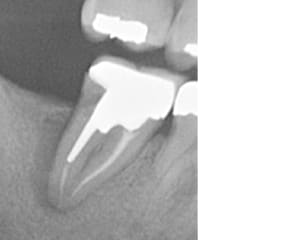

Capture d’écran 2025-10-07 222822.jpg